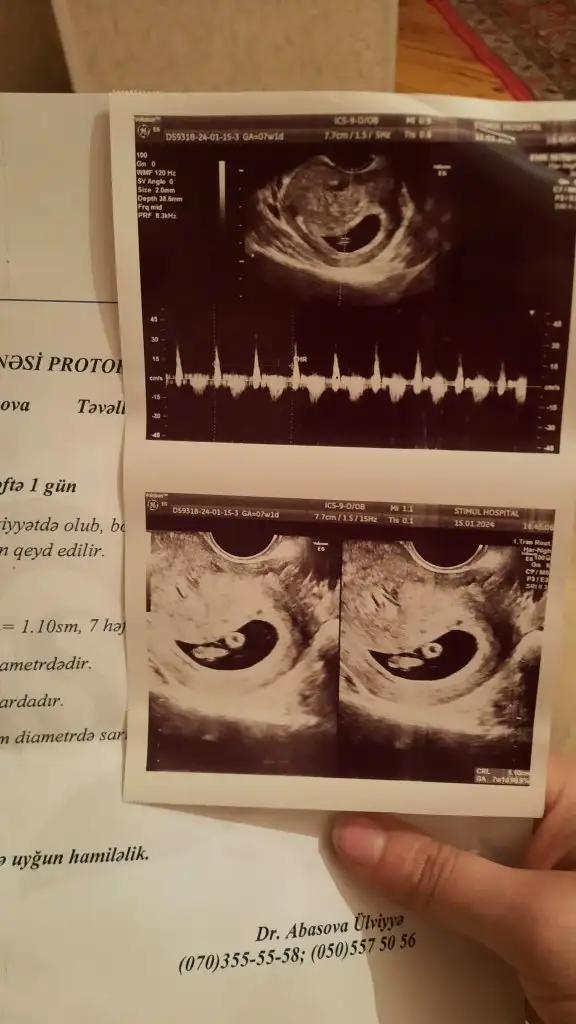

7+1 tahmin yapabilir misiniz Hülya hanımCanîm kıza çok benziyo hayırlısı olsun inşallah senne hissediyosun

Burada bebeğin konumununa göre yorum yapmışlar ama ramzi teorisi plasentanın konumuna göre bilgi veriyor diye biliyorum ben. Plasentanın da nerede olduğunu göremedim 2 gündür:)Konu biteli yıllar olmuş ama belki yorum gelir 7+4 karındanEki Görüntüle 3454856